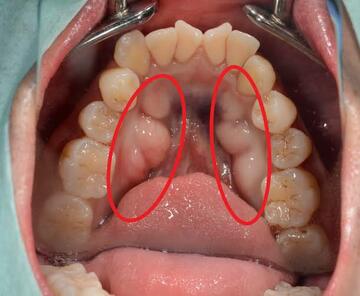

写真の左上辺りの歯🦷がくさび状に削れているの見えますか?

これ、歯ブラシでこする力で

歯が削れてしまっているんです。

この画像の様に、歯茎との境目がけずれる事が多いのですが、なぜこの場所かと言うと

エナメル質とセメント質の境目だからです。

エナメル質はすっごく硬くて鉄よりも硬いんですが、セメント質は、それよりも柔らかい

そんな境目をゴシゴシと磨く事で歯がすり減ってしまうんです。